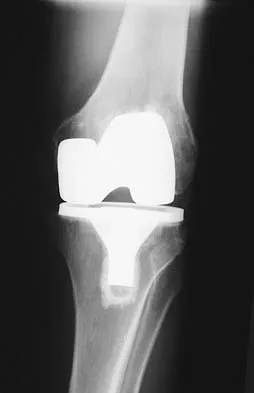

Question 76

A 75-year-old woman who fell on her right knee now reports pain and is unable to bear weight. History reveals that she underwent total knee arthroplasty on the right knee 6 years ago. Radiographs are shown in Figure 5. Management should now consist of

Explanation

The radiographs show a loose femoral component with an associated medial condyle distal femoral fracture. The treatment of choice is open reduction and internal fixation with revision of the femoral component because of the femoral component loosening. Moran MC, Brick GW, Sledge CB, et al: Supracondylar femoral fracture following total knee arthroplasty. Clin Orthop 1996;324:196-209. McLaren AC, DuPont JA, Schroeber DC: Open reduction internal fixation of supracondylar fractures above total knee arthroplasties using the intramedullary supracondylar rod. Clin Orthop 1994;302:194-198.